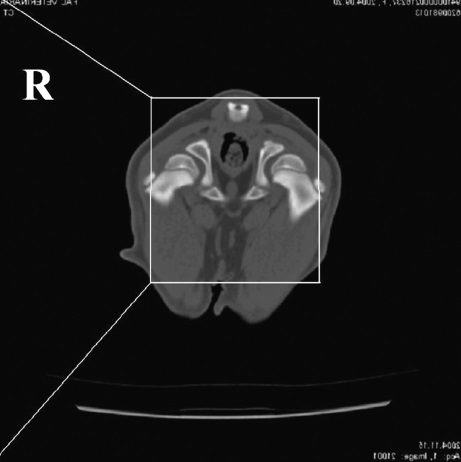

Diagnostyka

- Wywiad i badanie kliniczne – ocena kulawizny, bolesności i zakresu ruchu,

- RTG (rentgen) – podstawowe badanie, choć ze względu na złożoność stawu łokciowego, nie zawsze pozwala wykryć wszystkie zmiany

- TK (tomografia komputerowa) – bardzo dokładna ocena struktur kostnych, szczególnie przy podejrzeniu FCP

- Artroskopia – metoda inwazyjna, ale umożliwia jednocześnie diagnostykę i leczenie (usunięcie fragmentów chrząstki/kostnych).

Diagnostyka dysplazji

Rozpoznanie dysplazji opiera się na badaniu ortopedycznym oraz diagnostyce obrazowej. Najczęściej stosowane badania to:

- badanie kliniczne i ortopedyczne,

- badanie rentgenowskie (RTG),

- tomografia komputerowa (TK),

- artroskopia diagnostyczna.

Badania te pozwalają ocenić stopień zmian oraz zaplanować odpowiednie leczenie.